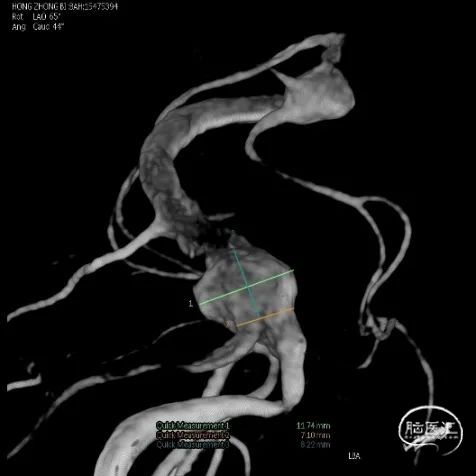

入院后立即行脑血管造影提示椎基底冗长扩张(基底动脉脑桥部分最宽处约5.2mm),伴有基底动脉多发动脉瘤,基底动脉尖动脉瘤(最大径约8mm)伴子囊和基底动脉下段动脉瘤(最大径约11mm)(图2)。

A

B

C

D

E